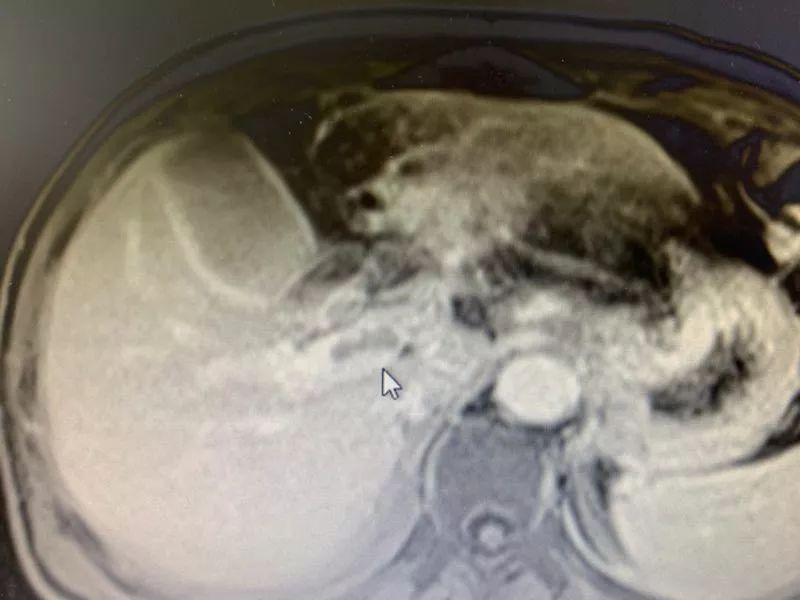

郑先生做完手术,两个星期后来复大的时候,通过磁共振看到肿瘤已经基本灭活了,通过增强磁共振也看到,门静脉癌栓也已经灭活缩小,门静脉主干已经恢复通畅了。